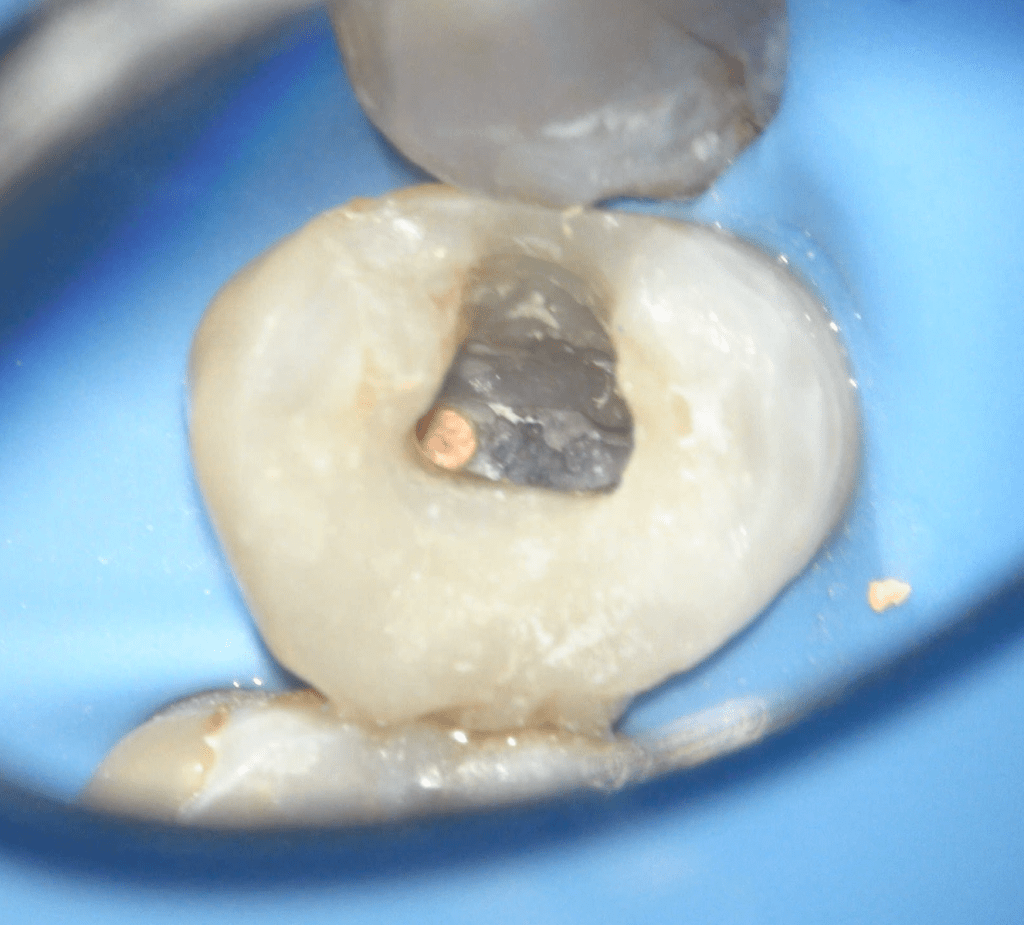

Fisura, remoción amalgama para explorar